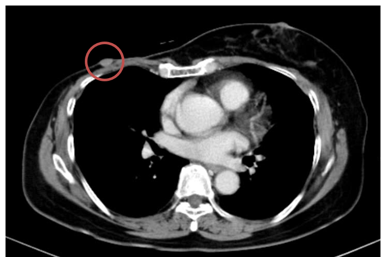

- Chụp cắt lớp vi tính ngực:

+ Thành ngực phải có nốt đặc kích thước khoảng 11x9mm – theo dõi tổn thương tái phát

Hình 1. Hình ảnh chụp CT ngực trước điều trị: Tổn thương tái phát thành ngực